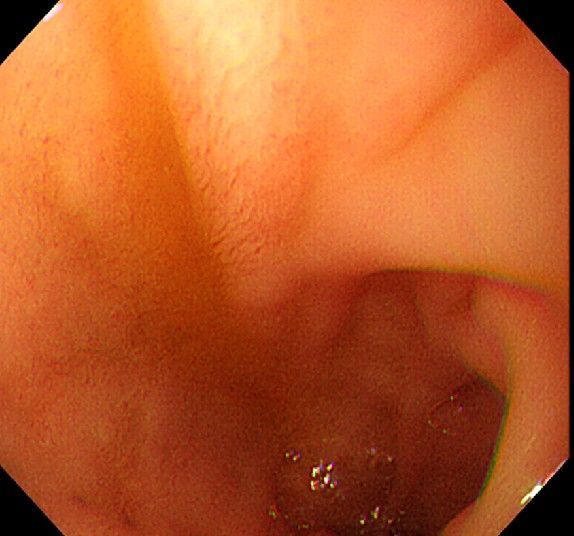

위 내시경을 찍었는데 위염 종류 사진을 알 수 있을까요? (사진 많습니다..)

한달 전 쯤에 소화불량과 속쓰림이 3개월 동안 약을 먹어도 낫지 않아 위 내시경을 찍었는데 위에 염증이 많이 있다는 이야기를 들었습니다...그런데 상태가 얼마나 안 좋은지 어떤 종류의 위염인지에 대해서는 물어봐도 안 알려주셔서 여기에라도 올려서 여쭈어봅니다... 제 상태가 얼마나 심각한 걸까요..

사진상으로 보아서는 정상에 가까운 점막상태이거나 약간의 표재성 위염이 있는 정도로 보입니다.

홍반성 위염이 있으며 경증의 역류성 식도염이 있습니다